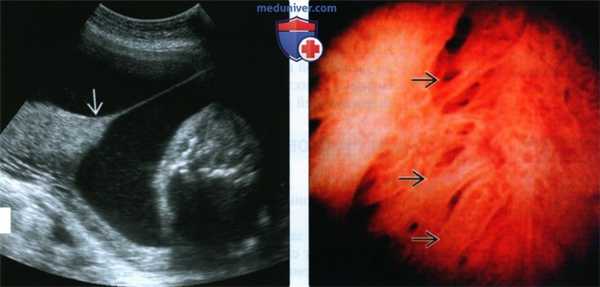

(Слева) УЗИ. Частичная имплантация плаценты поверх синехии. Данный феномен наблюдается достаточно часто и не оказывает отрицательного влияния на исходы.

(Справа) Изображение, полученное во время гистероскопии. Отмечаются фиброзные тяжи, проходящие через полость матки. Синехии могут стать причиной бесплодия, поэтому для повышения шансов наступления беременности внутриматочные синехии удаляют.